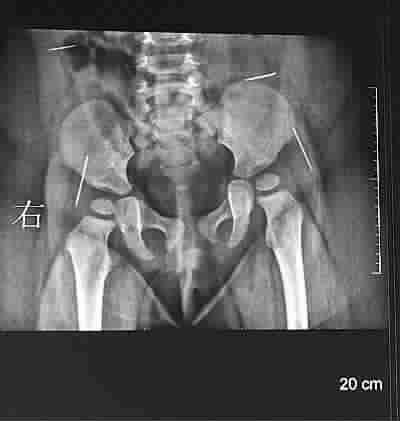

X片显示,女婴体内有四根针状金属物 图 TP

原来7月22日,由于小雨欣一直哭闹,家人在哄她睡觉时在其臀部发现了一根没有针鼻的缝衣针,于是带孩子到淮安市第一人民医院就诊,医生在为小雨欣做X光检查时发现,其体内还有四根针状金属物,遂建议到市妇幼保健院做手术。